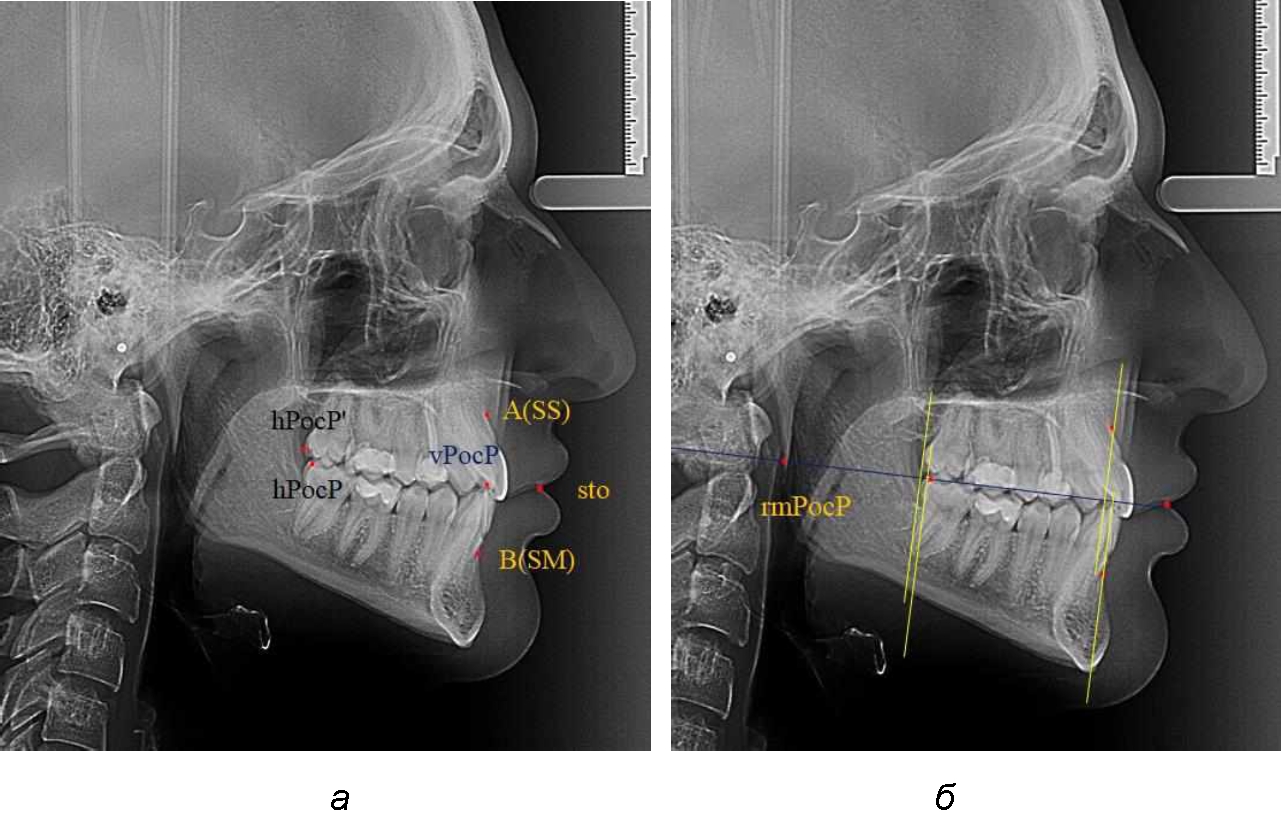

При сагиттальной патологии прикуса встречались варианты, при которых отмечалось равенство либо не равенство альвеолярно-ден-тальных размеров челюстей. Однако вне зависимости от этого, как правило, была отмечена разница в положении челюстей, измеряемая от конструируемой точки «rmРOcP» до точек апикальных базисов по Downs. С дистальной окклюзией было 20 снимков и с мезиальной окклюзией – 19 снимков.

Характерной особенностью мезиальной окклюзии было увеличение расстояния между проекционными апикальными точками, при котором существенно смещалась кпереди нижняя челюсть, а Wits-число имело отрицательные значения. Также дистальная точка нижнего моляра была расположена кпереди от верхней дистальной точки окклюзии второго моляра. Относительно равными считались показатели альвеолярно-дентальных размеров, при которых разница не превышала 1,5 мм. Тем не менее расстояние «rmРOcP-B(SM)» превышало расстояние «rmРOcP-A(SS)» в среднем по группе на (6,87 ± 1,62) мм, что свидетельствовало об аномалии положения челюстей, при котором визуально нижняя челюсть располагалась впереди верхней челюсти (рис. 3).

Рис. 3. Положение апикальных точек и челюстей при мезиальной окклюзии с равными (а) и разными (б) альвеолярно-дентальными размерами зубо-челюстных дуг

В тех случаях, когда при мезиальной окклюзии альвеолярно-дентальные размеры были различными, размер нижней челюсти превышал аналогичный параметр верхней челюсти в среднем на (3,74 ± 1,28) мм.